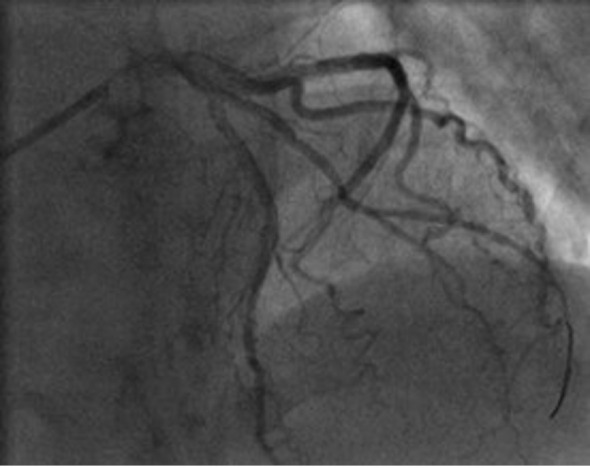

Case report: A 73-year-old patient, without comorbidities, was hospitalized for acute non ST-elevation myocardial infarction. Coronary angiography showed subocclusion of the first diagonal branch (culprit lesion) while the other epicardial coronary arteries were without stenosis. Multiple predilatations of the target vessel were performed, and as it was a vessel with a diameter of less than 2 mm, no stent was placed. The final angiogram showed normal flow and good morphological result. Half an hour after the procedure, cardiac tamponade and cardiorespiratory arrest developed. Emergency pericardiocentesis was performed and after the return of spontaneous circulation, emergency recoronarography was performed. It showed perforation of the diagonal branch with contrast extravasation. Coronary coil was applied proximal to the perforation site. Perforation repair and hemodynamic stabilization were achieved.